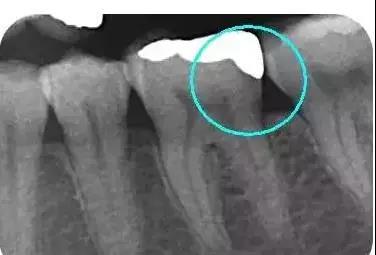

从下面这张X线中可以看出,嵌体远中边缘没有悬突,与牙体边缘密合相接。